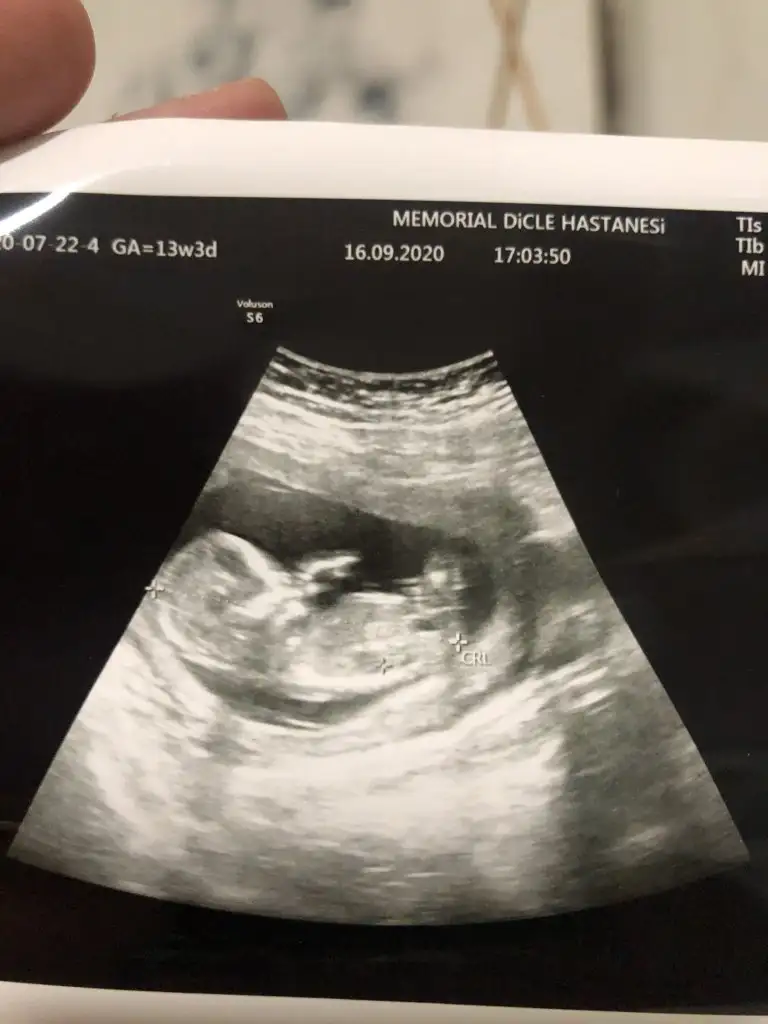

yeni bi ultrason resmi ile merhaba. :) hala cinsiyeti tam belli değil sadece bir doktor kıza benziyor dedi ama net değil dedi tekrar merak ettim :)

Yine hic net degil doktor.gordum dedi ama yorum mersk ediyorum doktor yuzdede vermedi netde demedi ama bilemedim belki bisiyler dersin son kez cnm bikac kezde atmıştım doktor yine ultrason goruntusu vermedi net goruntu yakalayamadi diye ben ekrani cektim Ikra meyra Ikra meyra 13+4

20200916_174747.jpg

Yine hic net degil doktor.gordum dedi ama yorum mersk ediyorum doktor yuzdede vermedi netde demedi ama bilemedim belki bisiyler dersin son kez cnm bikac kezde atmıştım doktor yine ultrason goruntusu vermedi net goruntu yakalayamadi diye ben ekrani cektim Ikra meyra Ikra meyra 13+4Eki Görüntüle 2691630

Nub iyi gozukmoyor ama sanki erkek